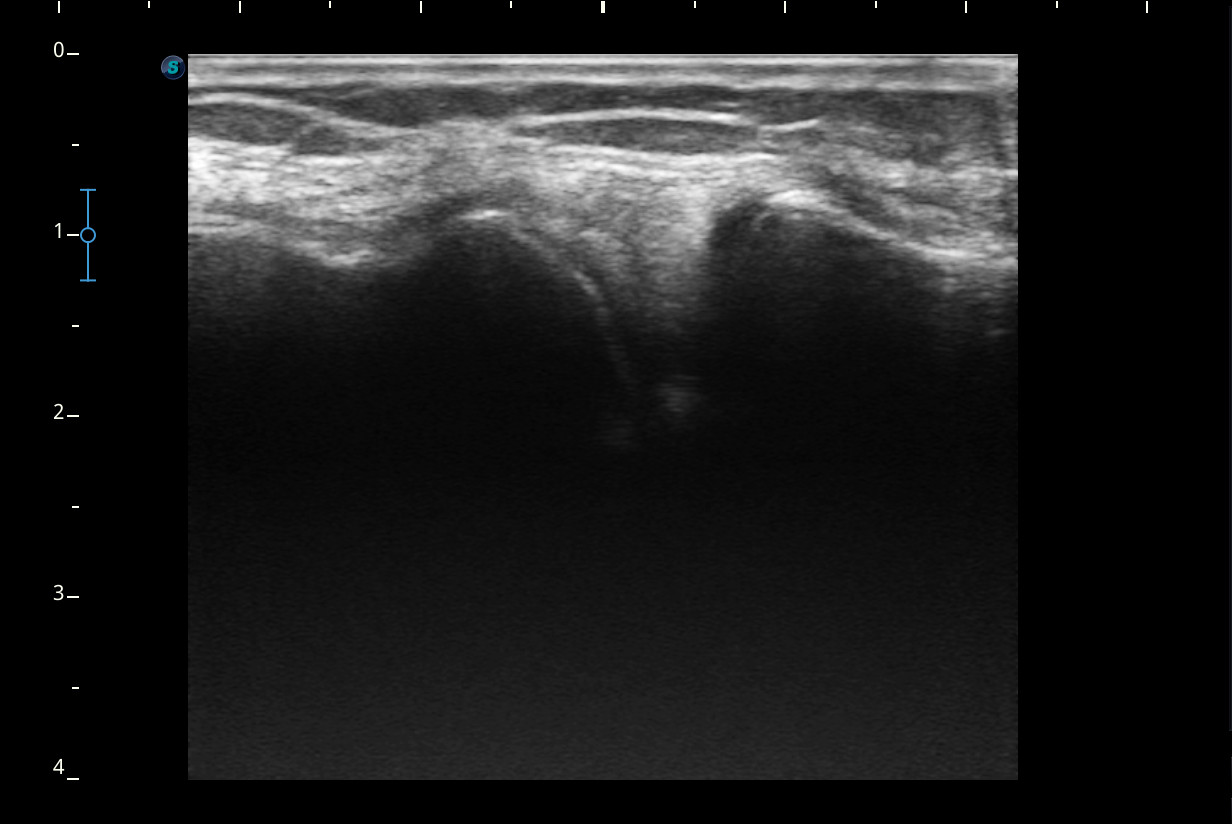

Se realiza ecografía de rodilla.

Descripción de los hallazgos ecográficos y las imágenes más relevantes para la resolución del caso

Rodilla sin derrame articular. No se aprecian lesiones en Ligamentos colaterales. Ligamento rotuliano sin hallazgos valorables. Rotura menisco interno y dudosa fisura menisco externo. Tendones rotuliano y cuadricipital normales.